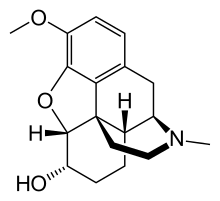

- Semi-synthetic opioids: created from either the natural opiates or morphine esters, such as hydromorphone, hydrocodone, oxycodone, oxymorphone, ethylmorphine and buprenorphine;